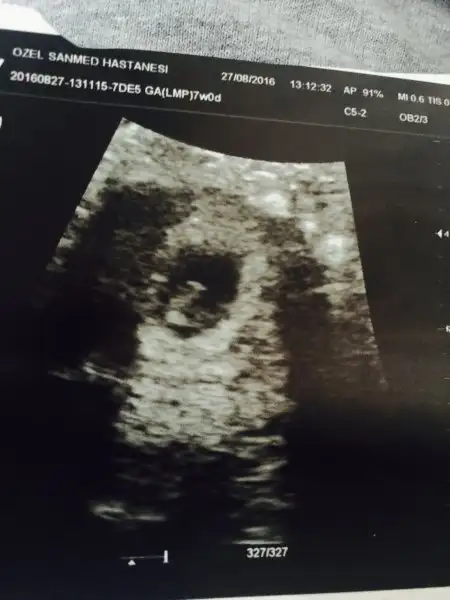

6 hftalik fotoğraf çok karanlık ben bile bebeği görmedim hiç iyi çekmemiş doktor bunda belli olmuyor mu6 haftalık fotoyu at cnm

Bu resim 12.haftalıktı ama çok yakınlaştırarak çekti 16+3 te gittim söylemedi yine12-13 haftalık bi foto atsana cnm

6 haftalık karından canım benim deHavalianne__